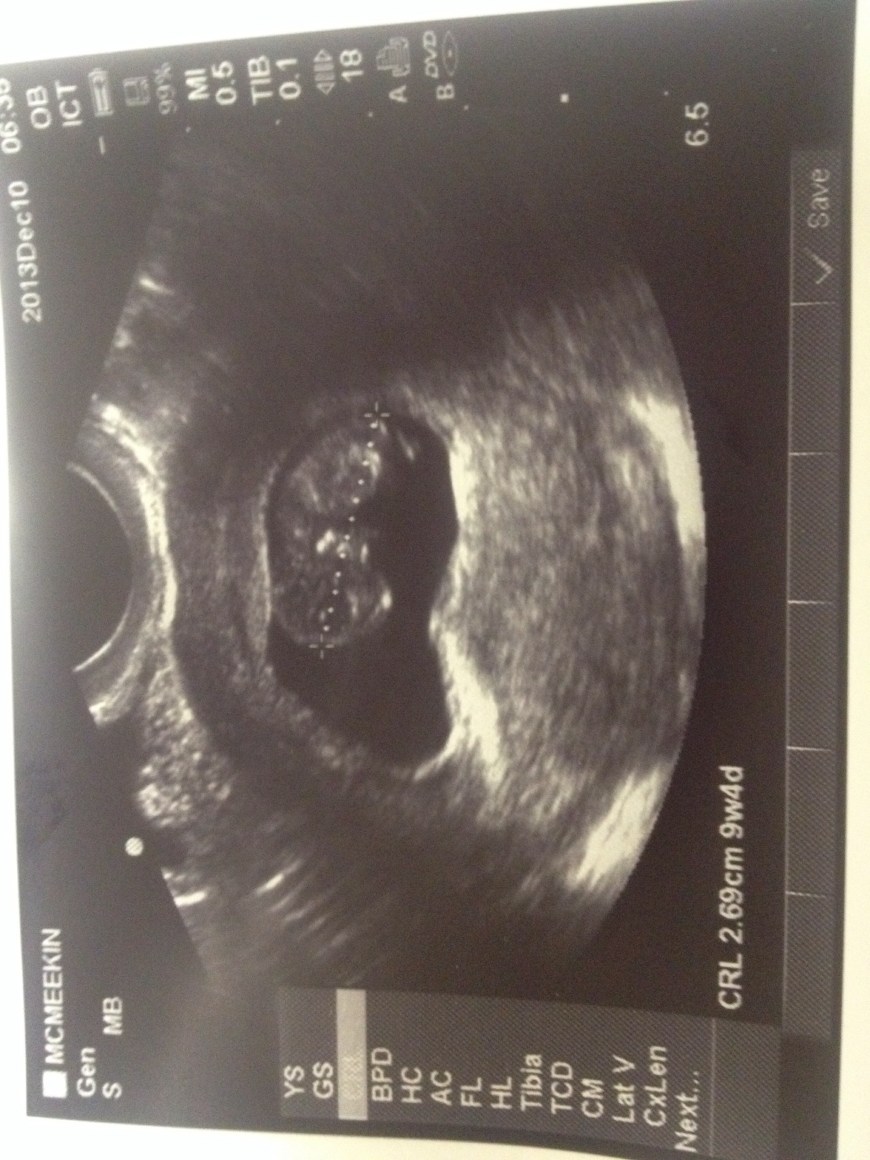

The worst year of my life is over. A new year has begun and I find myself in a very similar position that I was this time last year: pregnant. 13 and a half weeks pregnant to be exact. Over the moon happy, and more scared than I have ever been in my life.

I have been avoiding my blog since I found out, because I have been so scared to openly admit to the world (and myself) that Everlee’s little brother or sister is nestled quietly in my belly. But with a new year comes new hope. After every great storm, there is a rainbow. I am so grateful to be pregnant with my rainbow baby.

2014 will bring many doctors appointments, lots of bed rest, a lot of anxiety and hopefully in June, a little healthy and alive brother or sister for my darling little girl.